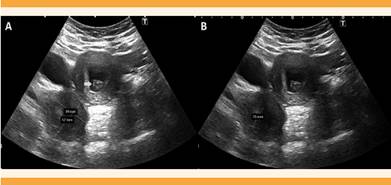

En la ecografía abdominopélvica se sospechó una malformación congénita uterina, pues se visualizó el útero izquierdo ligeramente tubular, de tamaño normal, con un pólipo endometrial en su interior, y adyacente a la imagen se observó una masa compatible con hemiútero derecho, de 52 x 49 mm, con contenido líquido hematológico retenido (hematometra) de 25 mm. El hemiútero no tenía conexión aparente con el cuello uterino ni con la porción contralateral del útero (Figura 1). El ovario izquierdo se visualizó de tamaño y características normales, con microfolículos y eje mayor de 3.2 cm, rodeando por fuera y por delante al ovario derecho, también de tamaño y aspecto normales; se observó una estructura quística alargada y en forma de codo, con contenido ecogénico de 65 x 15 mm, sugerente de hematosalpinx (Figura 2). La tomografía abdominopélvica confirmó la coexistencia del hemiútero derecho, de 55 x 54 mm, hipervascular, degenerado, con colección hemorrágica interna de 30 mm (Figura 3), e hidrosalpinx derecho. La ecografía y la tomografía no demostraron malformaciones renales. Figura 4

Figura 1 A) Hemiútero derecho de 52 x 49 mm. Hemiútero izquierdo, en plano más anterior, de aspecto normal, con pólipo endometrial en su interior (flecha). B) Colección líquida y heterogénea de 25 mm en el interior del hemiútero derecho, compatible con hematometra.